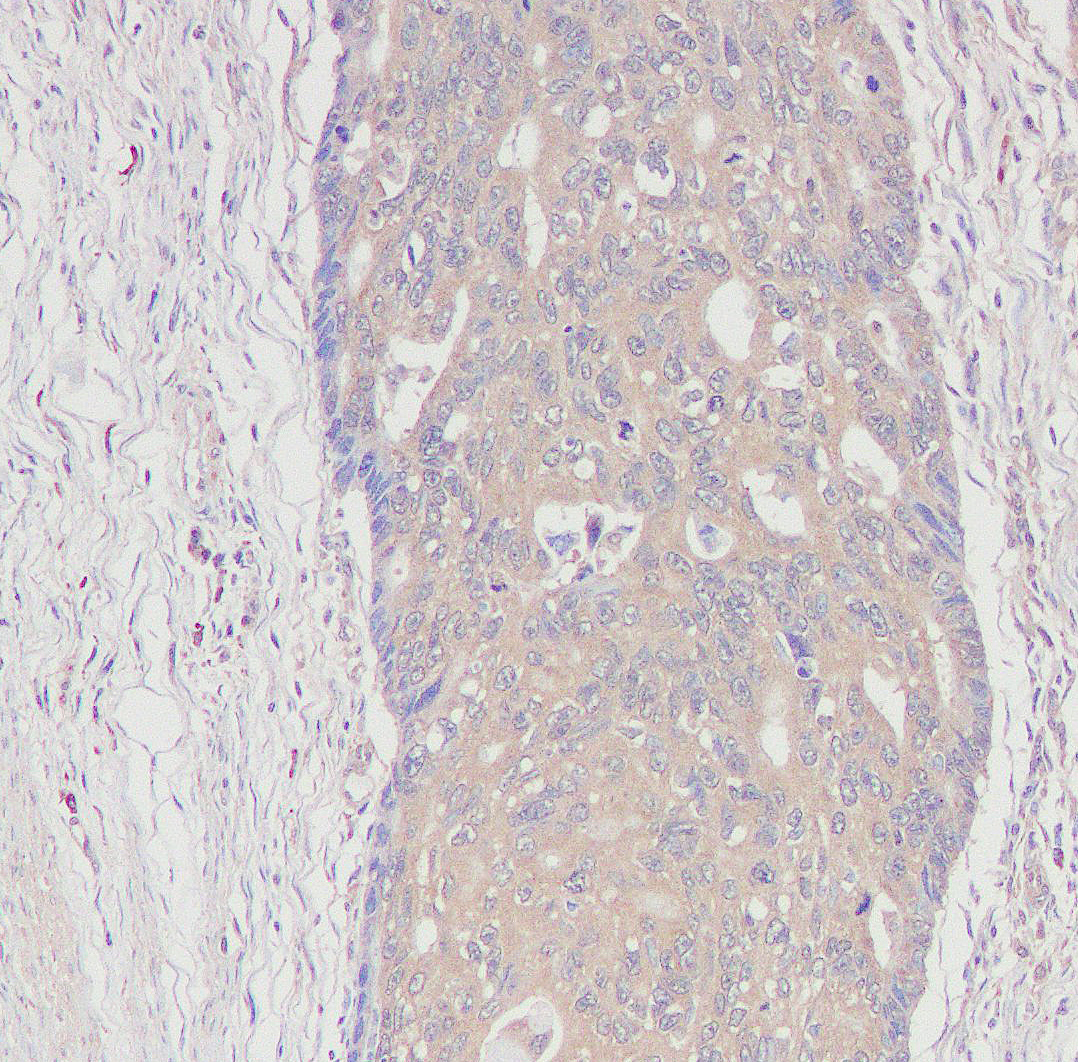

Formalin-fixed, paraffin-embedded human breast carcinom tissue stained for Phospho-PI3 Kinase p85α(Tyr607) using 12057 at 1/100 dilution in immunohistochemical analysis.